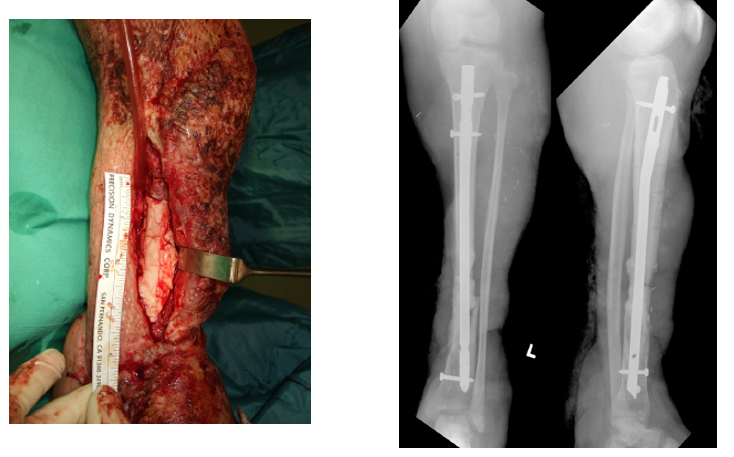

53y  M  车祸损伤左侧胫腓骨远端开放性粉碎性骨折Gustilo IIIB;AO 43-C3

Stage I清创、外支架固定

• 骨缺损6cm

• 软组织缺损

• 距骨关节面外露

带抗生素骨水泥旷置游离股薄肌瓣覆盖

术后复查外支架维持稳定Spacer位置理想力线良好